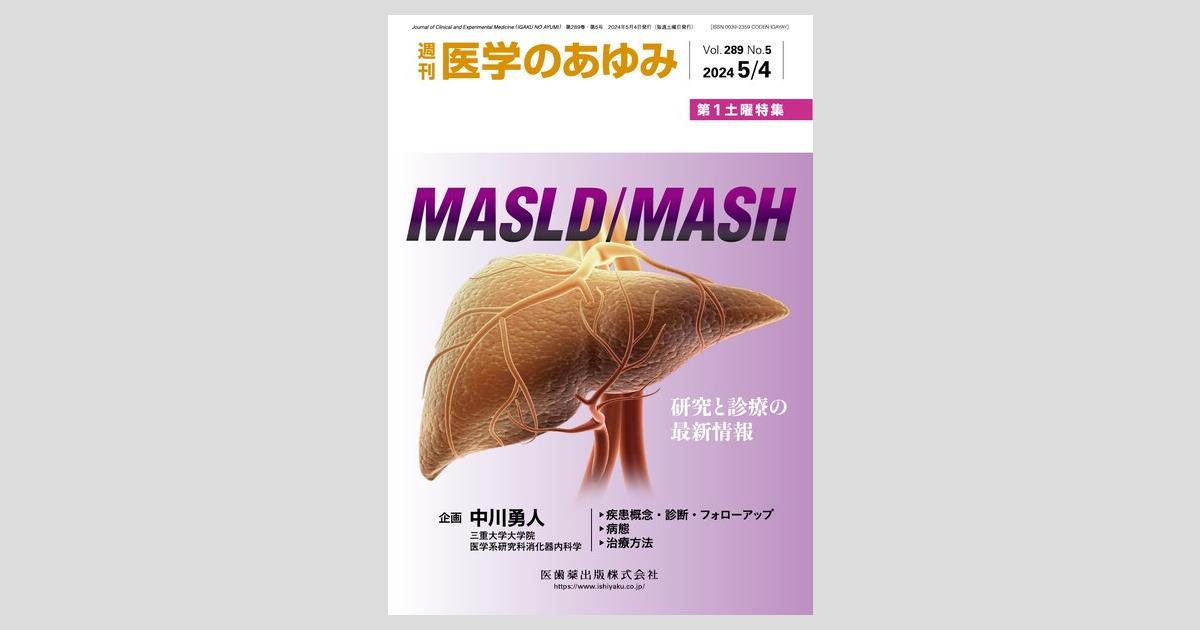

Amazon.co.jp: 義歯に血の通うまで アルプス歯科の総義歯製作。Amazon.co.jp: 義歯に血の通うまで アルプス歯科の総義歯製作。Amazon.co.jp: 義歯に血の通うまで : 中込敏夫, 向井道夫: 本。令和六年度 魚沼産コシヒカリ5キロと新潟県産コシヒカリ5キロ、計10キロ。株式会社 医療情報研究所 | 早くて簡単!総義歯吸着の神技。GPによる複製義歯を利用した総義歯製作 冨田 知孝先生。総義歯づくり すいすいマスター 総義歯患者の「何ともない」を。噛める、痛くない、審美的入れ歯で快適生活 「入れ歯110番。41dgXQG+tOL._BO30,255,255,。医学のあゆみ 289巻5号 MASLD/MASH ─研究と診療の最新情報 5月。総義歯の病理―基礎と臨床から導き出された総義歯製作法。学術04(最終回)「医科歯科介護」連携時代の保険で『噛める総。総義歯の病理―基礎と臨床から導き出された総義歯製作法。サンバレー書房カバーは若干スレあり中身は綺麗です定価20000円神経質な方はご遠慮ください#歯科医師#義歯#歯科技工士